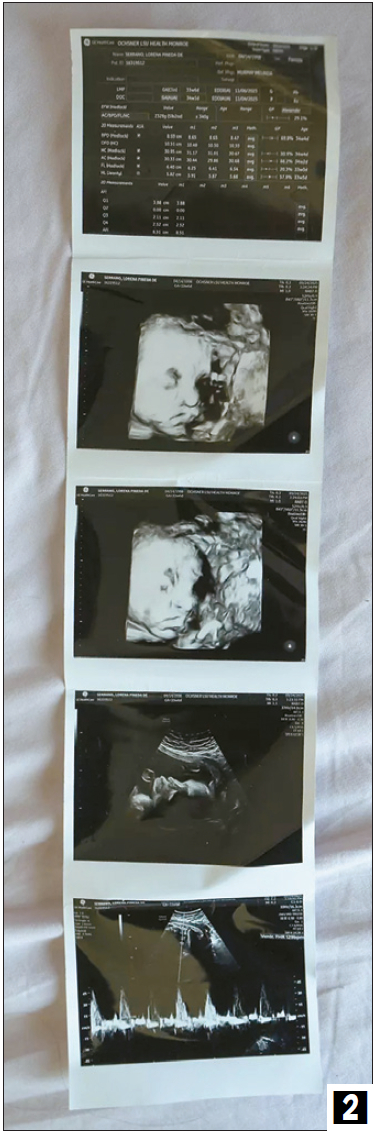

피네다가 구금 중 촬영된 자신의 태아 초음파 이미지. [칼라 가체트/LA타임스 객원기자]